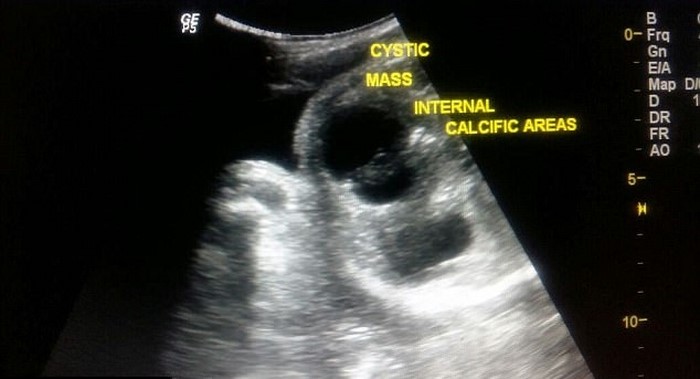

En la ciudad india de Thana, nació un bebé único. No obstante, durante uno de los exámenes de rutina, se reveló que un embrión de más crecía adherido al cuerpo del bebé nonato…

Este fenómeno se conoce como «fetus in fetus». En toda la historia, se han reportado unos 200 casos de este tipo.

La radióloga Bhavna Torat vio una anomalía durante el examen de la joven embarazada, de 19 años. Después del nacimiento, el bebé se sometió a una cirugía, durante la cual un gemelo de 7 centímetros se retiró de su cuerpo, con un peso de unos 150 g.